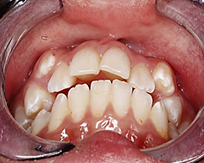

El análisis de discrepancia se realizó sobre los modelos de estudio obteniendo una discrepancia superior de - 4mm y una discrepancia inferior de -1.8 mm (G). En la ortopantomografía se observa que el seno maxilar izquierdo aparece velado, presencia de los 4 gérmenes de los terceros molares, cornetes hipertróficos, no se visualiza ensanchamiento del ligamento periodontal, no existen patologías periapicales (H). Los estudios cefalométricos que se realizaron fueron Rickkets, Jaraback y Steiner, obteniendo como resumen: patrón esqueletal Clase II por protrusión maxilar, a nivel de incisivos: protrusión y proinclinación del incisivo superior e inferior, VERT: +0,69 dándonos un patrón facial: braquifacial suave, en las esferas rotacionales de Jarabak: 54% indicándonos una tendencia a crecimiento rotacional posterior (I).

A través de los cortes tomográficos (Figura 3) se pudo observar que la rama mandibular derecha medía 43.85 mm y la izquierda 39.53 mm dando una diferencia de 4.34 mm lo que evidencia que la asimetría que presenta la paciente es a causa de la discrepancia de tamaño de las ramas mandibulares (A).

En el corte a nivel de la articulación temporomandibular izquierda se observó un aplanamiento del cóndilo con áreas de cambios osteoartríticos leves (B); en la articulación temporomandibular derecha el cóndilo se encuentra con una severa osteoartritis que muestra una imagen hipodensa a nivel condilar compatible con un quiste subcondral (C).